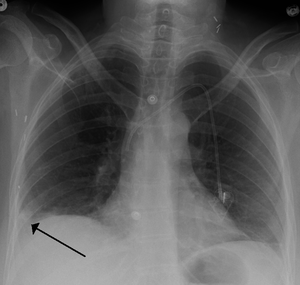

يتم من خلال الأعراض المذكورة آنفاً وعن طريق الفحوصات الشعاعية كصورة الصدر الشعاعية, والتصوير الطبقي المحوري أو من خلال الصور النووية للرئتين، والفحوصات المخبرية الأخرى التي تساعد في التشخيص تعداد الدم الكامل وسرعة تجلط الدم، كما تجرى بعض التحاليل الدموية كإجراء وقائي ومنها فحص وظائف الكبد والكلى ومعدلات الشوارد وسرعة تسفل الدم. ومسح التهوية والتروية الرئوي هو شكل من التصوير الشعاعي التشخيصي هدفه تقييم التروية والتهوية في الرئتين ويستخدم في تشخيص الانصمام الرئوي. التصوير فوق الصوتي أو التخطيط التصواتي لأوعية الساق الدموية مهم لتقييم وجود أي خثار في أوردة الساق، يعد الإثبات بالإصابة بالخثار الوريدي العميق / جلطة الساق دليلاً هاماً على القابلية العالية للإصابة بالانصمام الرئوي. تخطيط القلب الكهربائي هو إجراء روتيني لأي مريض يأتي بألم في الصدر ويستخدم لإثبات أو نفي وجود احتشاء العضلة القلبية أو الذبحة الصدرية، كما لوحظ وجود 3 علامات كلاسيكية على تخطيط القلب الكهربائي في حالات الانصمام الرئوي وهي: موجة S كبيرة على القطب الأول I موجة Q كبيرة على القطب الثالث III موجة T معكوسة على القطب الثالث III ,7-8 ,3-5.[16]

التصوير الطبقي المحوسب

التصوير الطبقي المحوسب للرئة والمصحوب باستخدام الصبغة المشعة في الوريد أصبح واسع الانتشار والاستخدام في تشخيص المرضى المشتبه بإصابتهم بالانصمام الرئوي، لهذا النوع من التصوير حساسية تبلغ 83% ودقة نوعية تصل إلى 96%.[24].[25]